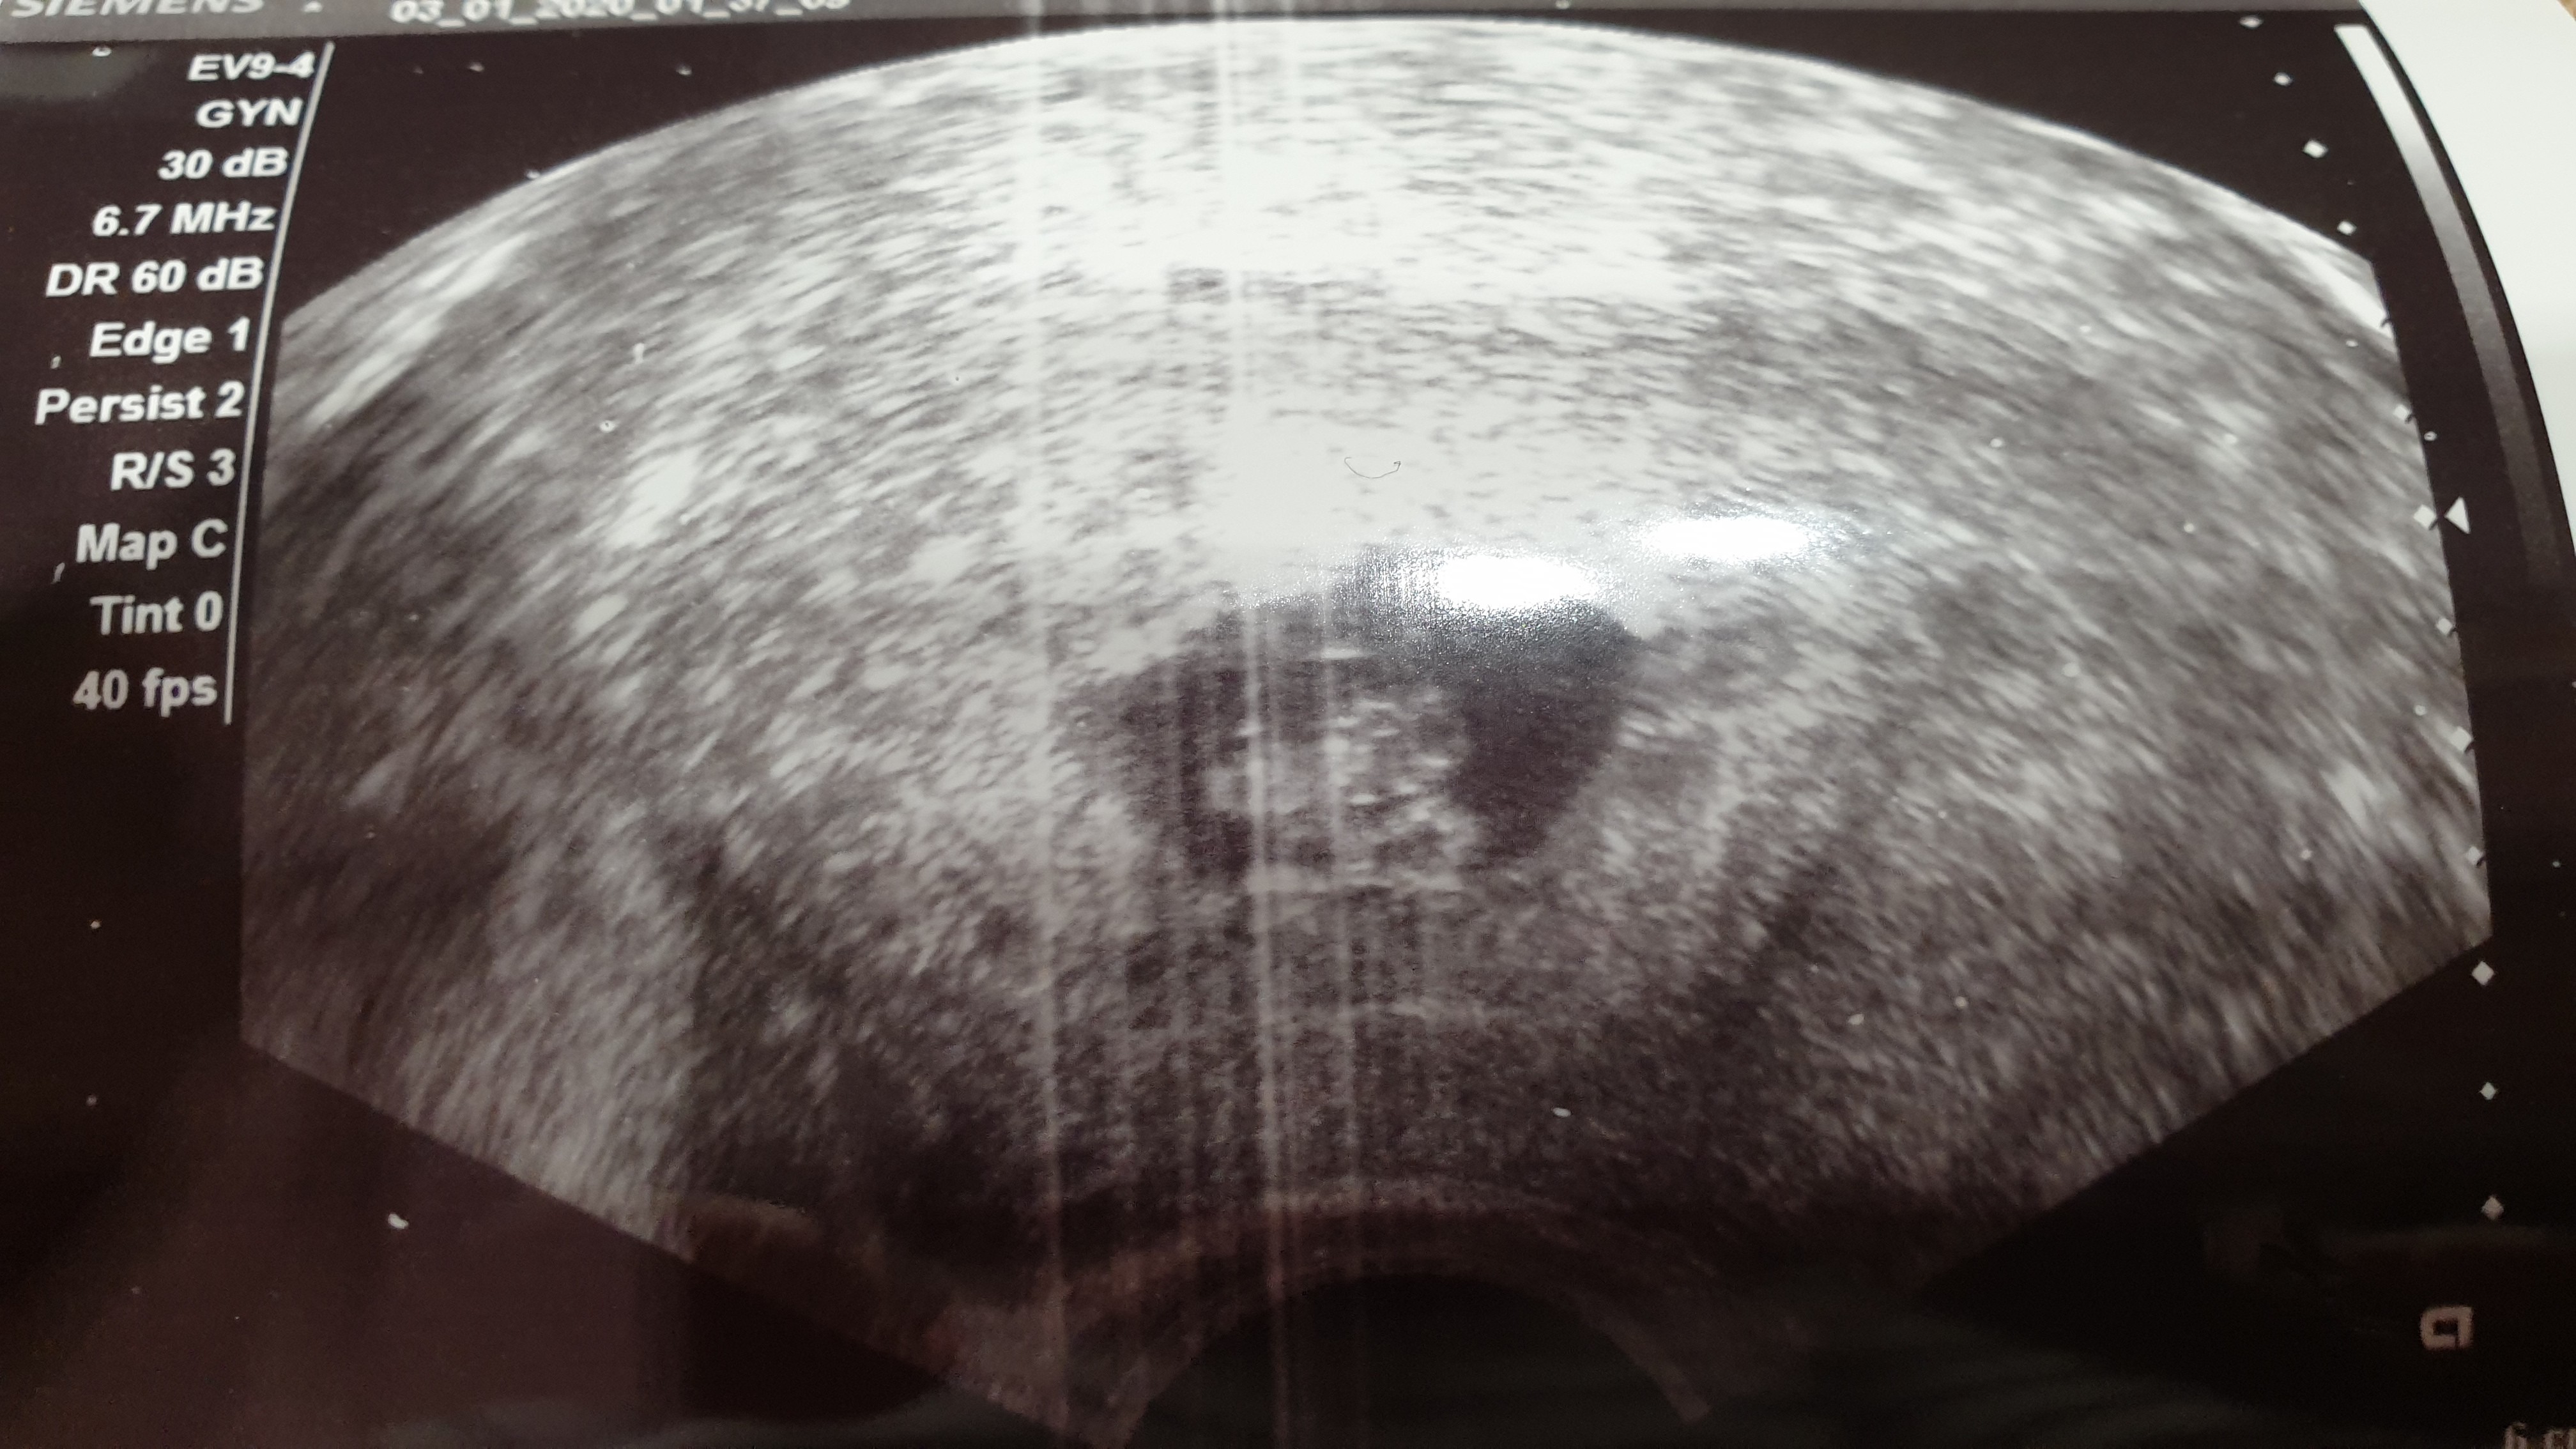

To i ja się pochwalę bo właśnie wróciliśmy z wizyty. Mamy serduszko!! Tętno 160 :D Wiek ciąży z usg 6t6d a wg OM 7t4d. Maluch ma 0.86 cm :D

• 20200102_193214.jpg

20200102_193214.jpg

1,3 MB · Wyświetleń: 106